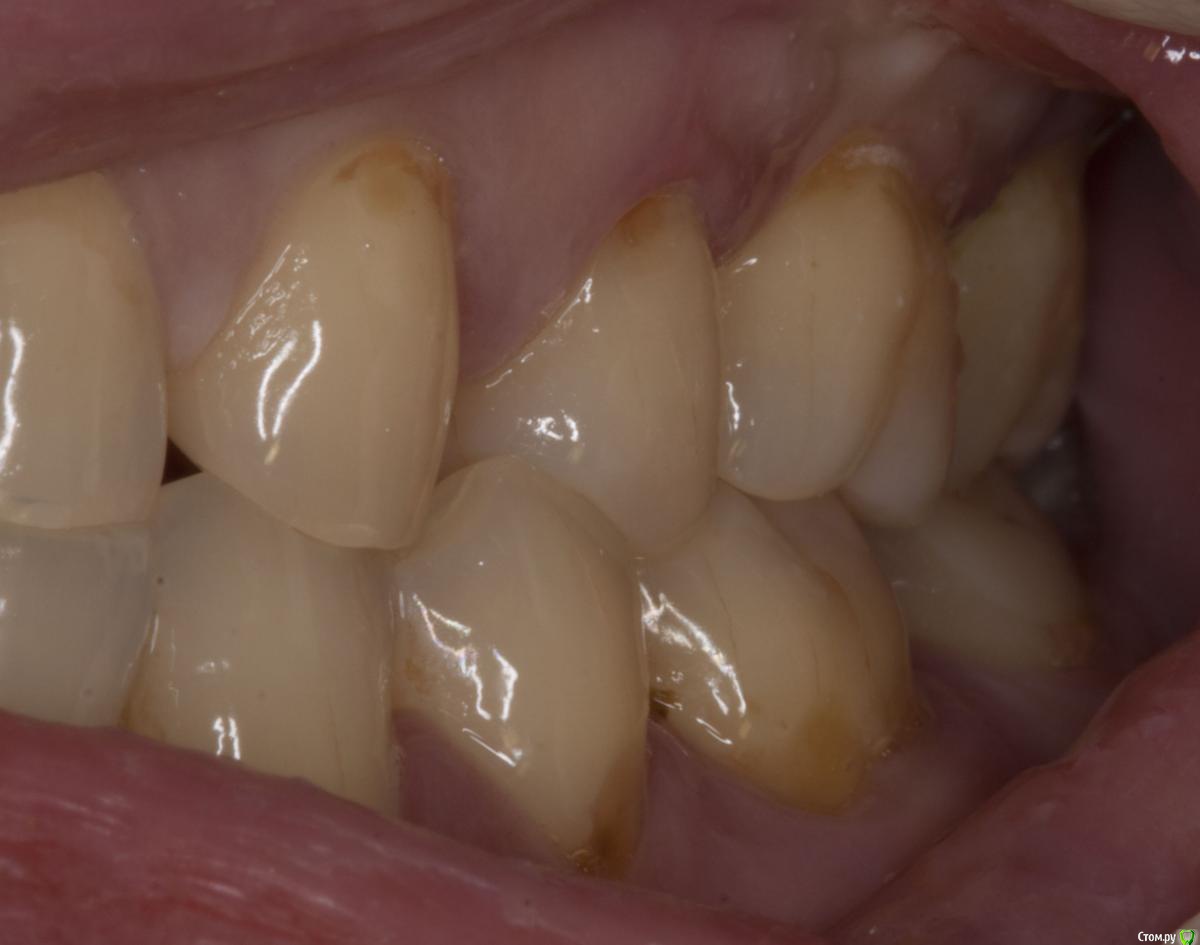

Sampson Опубликовано 29 июля, 2015 Поделиться Опубликовано 29 июля, 2015 (изменено) Зуб на удаление и диагностическое вскрытие. Пациент к ЛОРуФото зуба хочется увидеть. Пульпит может быть следствием пародонтита из-за оголения боковых ответвлений. Изменено 29 июля, 2015 пользователем Sampson Ссылка на комментарий

M@estro Опубликовано 29 июля, 2015 Поделиться Опубликовано 29 июля, 2015 (изменено) Травматический узел. Изменено 29 июля, 2015 пользователем M@estro 10 Ссылка на комментарий

M@estro Опубликовано 30 июля, 2015 Поделиться Опубликовано 30 июля, 2015 Паш, расскажи подробнее пожалуйста Пришла пациентка на прием, болит зуп. Сделали снимок , карман локально до 1 см глубиной. Подвижность 3 степени, обострение. Зуб целый. Ну челюстью подвигала - оппа! - вот и привет. Причем призналась. что сресяк у нее месяца 4 -5 усилился, вот и окончательно не выдержал. Вторая была девушка - тоже 2.6 зуб, но я не фотал её. Ситуация похожая, я тоже зуб вынул просто. Там вообще был целый моляр, ни дырочки в нем, ни пломбы. Год лечили от гайморита антибиотиками её лоры, потому как " все зубы интактные" . В поликлише в смотровом проглядели её этот зуб. Я удалил - через две недели пришла на приём с благодарностью - разложило нос ) Видел недавно её - гайморита нет и следа. Ссылка на комментарий

M@estro Опубликовано 3 августа, 2015 Поделиться Опубликовано 3 августа, 2015 но у вашем случае у антагониста пломба, а у паца тс нет пломбы на антагонисте. или там другая причина супраоклюзии? Я специально сделал серию фото, чтобы виден был перегруз 2.6 при левой латеротрузии. Ссылка на комментарий

diesel87 Опубликовано 4 августа, 2015 Поделиться Опубликовано 4 августа, 2015 Я специально сделал серию фото, чтобы виден был перегруз 2.6 при левой латеротрузии. как бороться с этим на ранних стадиях? Ссылка на комментарий

brg Опубликовано 9 августа, 2015 Поделиться Опубликовано 9 августа, 2015 как бороться с этим на ранних стадиях?Пришлифовывать, убирать сверх нагрузку. Ссылка на комментарий

M@estro Опубликовано 9 августа, 2015 Поделиться Опубликовано 9 августа, 2015 как бороться с этим на ранних стадиях? 1) Ортодонтия 2) Избирательное пришлифовывание Ссылка на комментарий